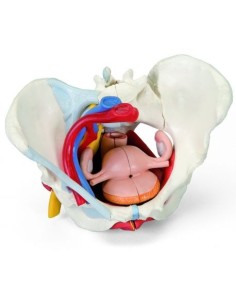

3B Modèle anatomique scientifique du bassin gravide, décomposable en 3 parties L20

3B Bassin scientifique, anatomique Modèle pour illustrer l'accouchement L30